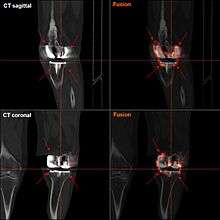

- Conventional radiograph: Rule out other conditions such as loosening and/or osteolysis.

- Radionucleotide Imaging: Technetium-99m Sulfur imaging combined with indium-111-labeled leukocytes probably offers improved specificity than either test alone. Gallium 67 scans alone have low sensitivity for infection. FDG-PET imaging has been shown to have variable specificity and sensitivity.

- Serology: Elevated serum C-reactive protein (CRP) and Erythrocyte Sedimentation Rate (ESR) more than three months following arthroplasty are good screening tests.[12]